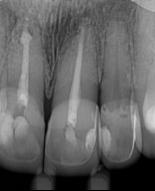

En la segunda sesión, 15 días después, realizamos la obturación convencional del tercio apical del canal con gutapercha, llenado de la cavidad reabsortiva con BIO-C ® REPAIR (Angelus, Londrina - Brasil) (Figura 7, 8 y 9), condensándolo contra las paredes con condensadores específicos y bolita de algodón humedecida y realizamos el sellado coronario con resina.

El BIO-C® REPAIR es un cemento reparador biocerámico listo para su uso. Se compone de silicato de calcio, aluminato de calcio, óxido de calcio, óxido de zirconio, óxido de hierro, dióxido

de silicio y agente de dispersión. El BIO-C® REPAIR presenta características superiores de adaptación marginal, biocompatibilidad, excelente radiopacidad y capacidad selladora en ambientes húmedos. Además de estas características, tiene como gran ventaja su facilidad de inserción a la cavidad reabsortiva

8 - Radiografia final

9 - Cavidad reabsortiva rellenada com BIO-C® REPAIR